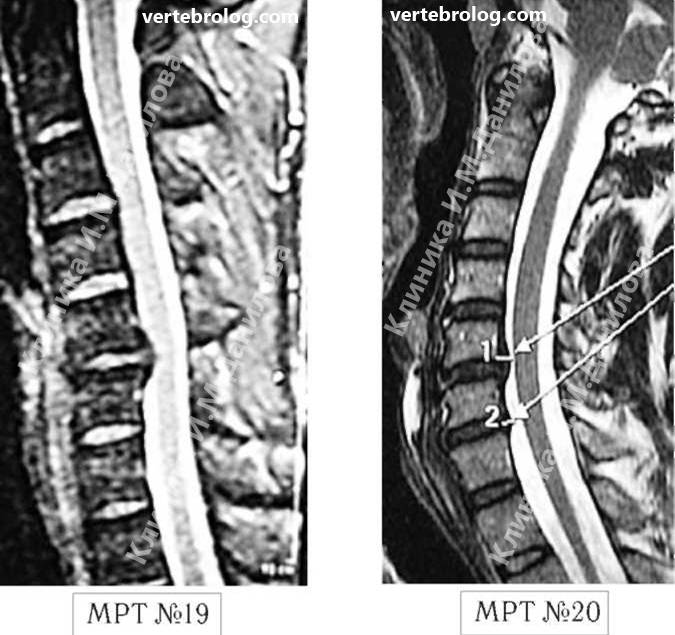

Мрт картина дегенеративно дистрофических изменений пояснично крестцового отдела позвоночника